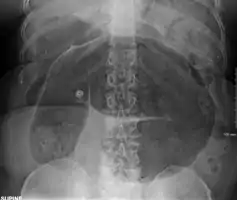

- Abdominal x-ray – tire-like shadow arising from right iliac fossa and passing to left

Plain X ray of a cecal volvulus